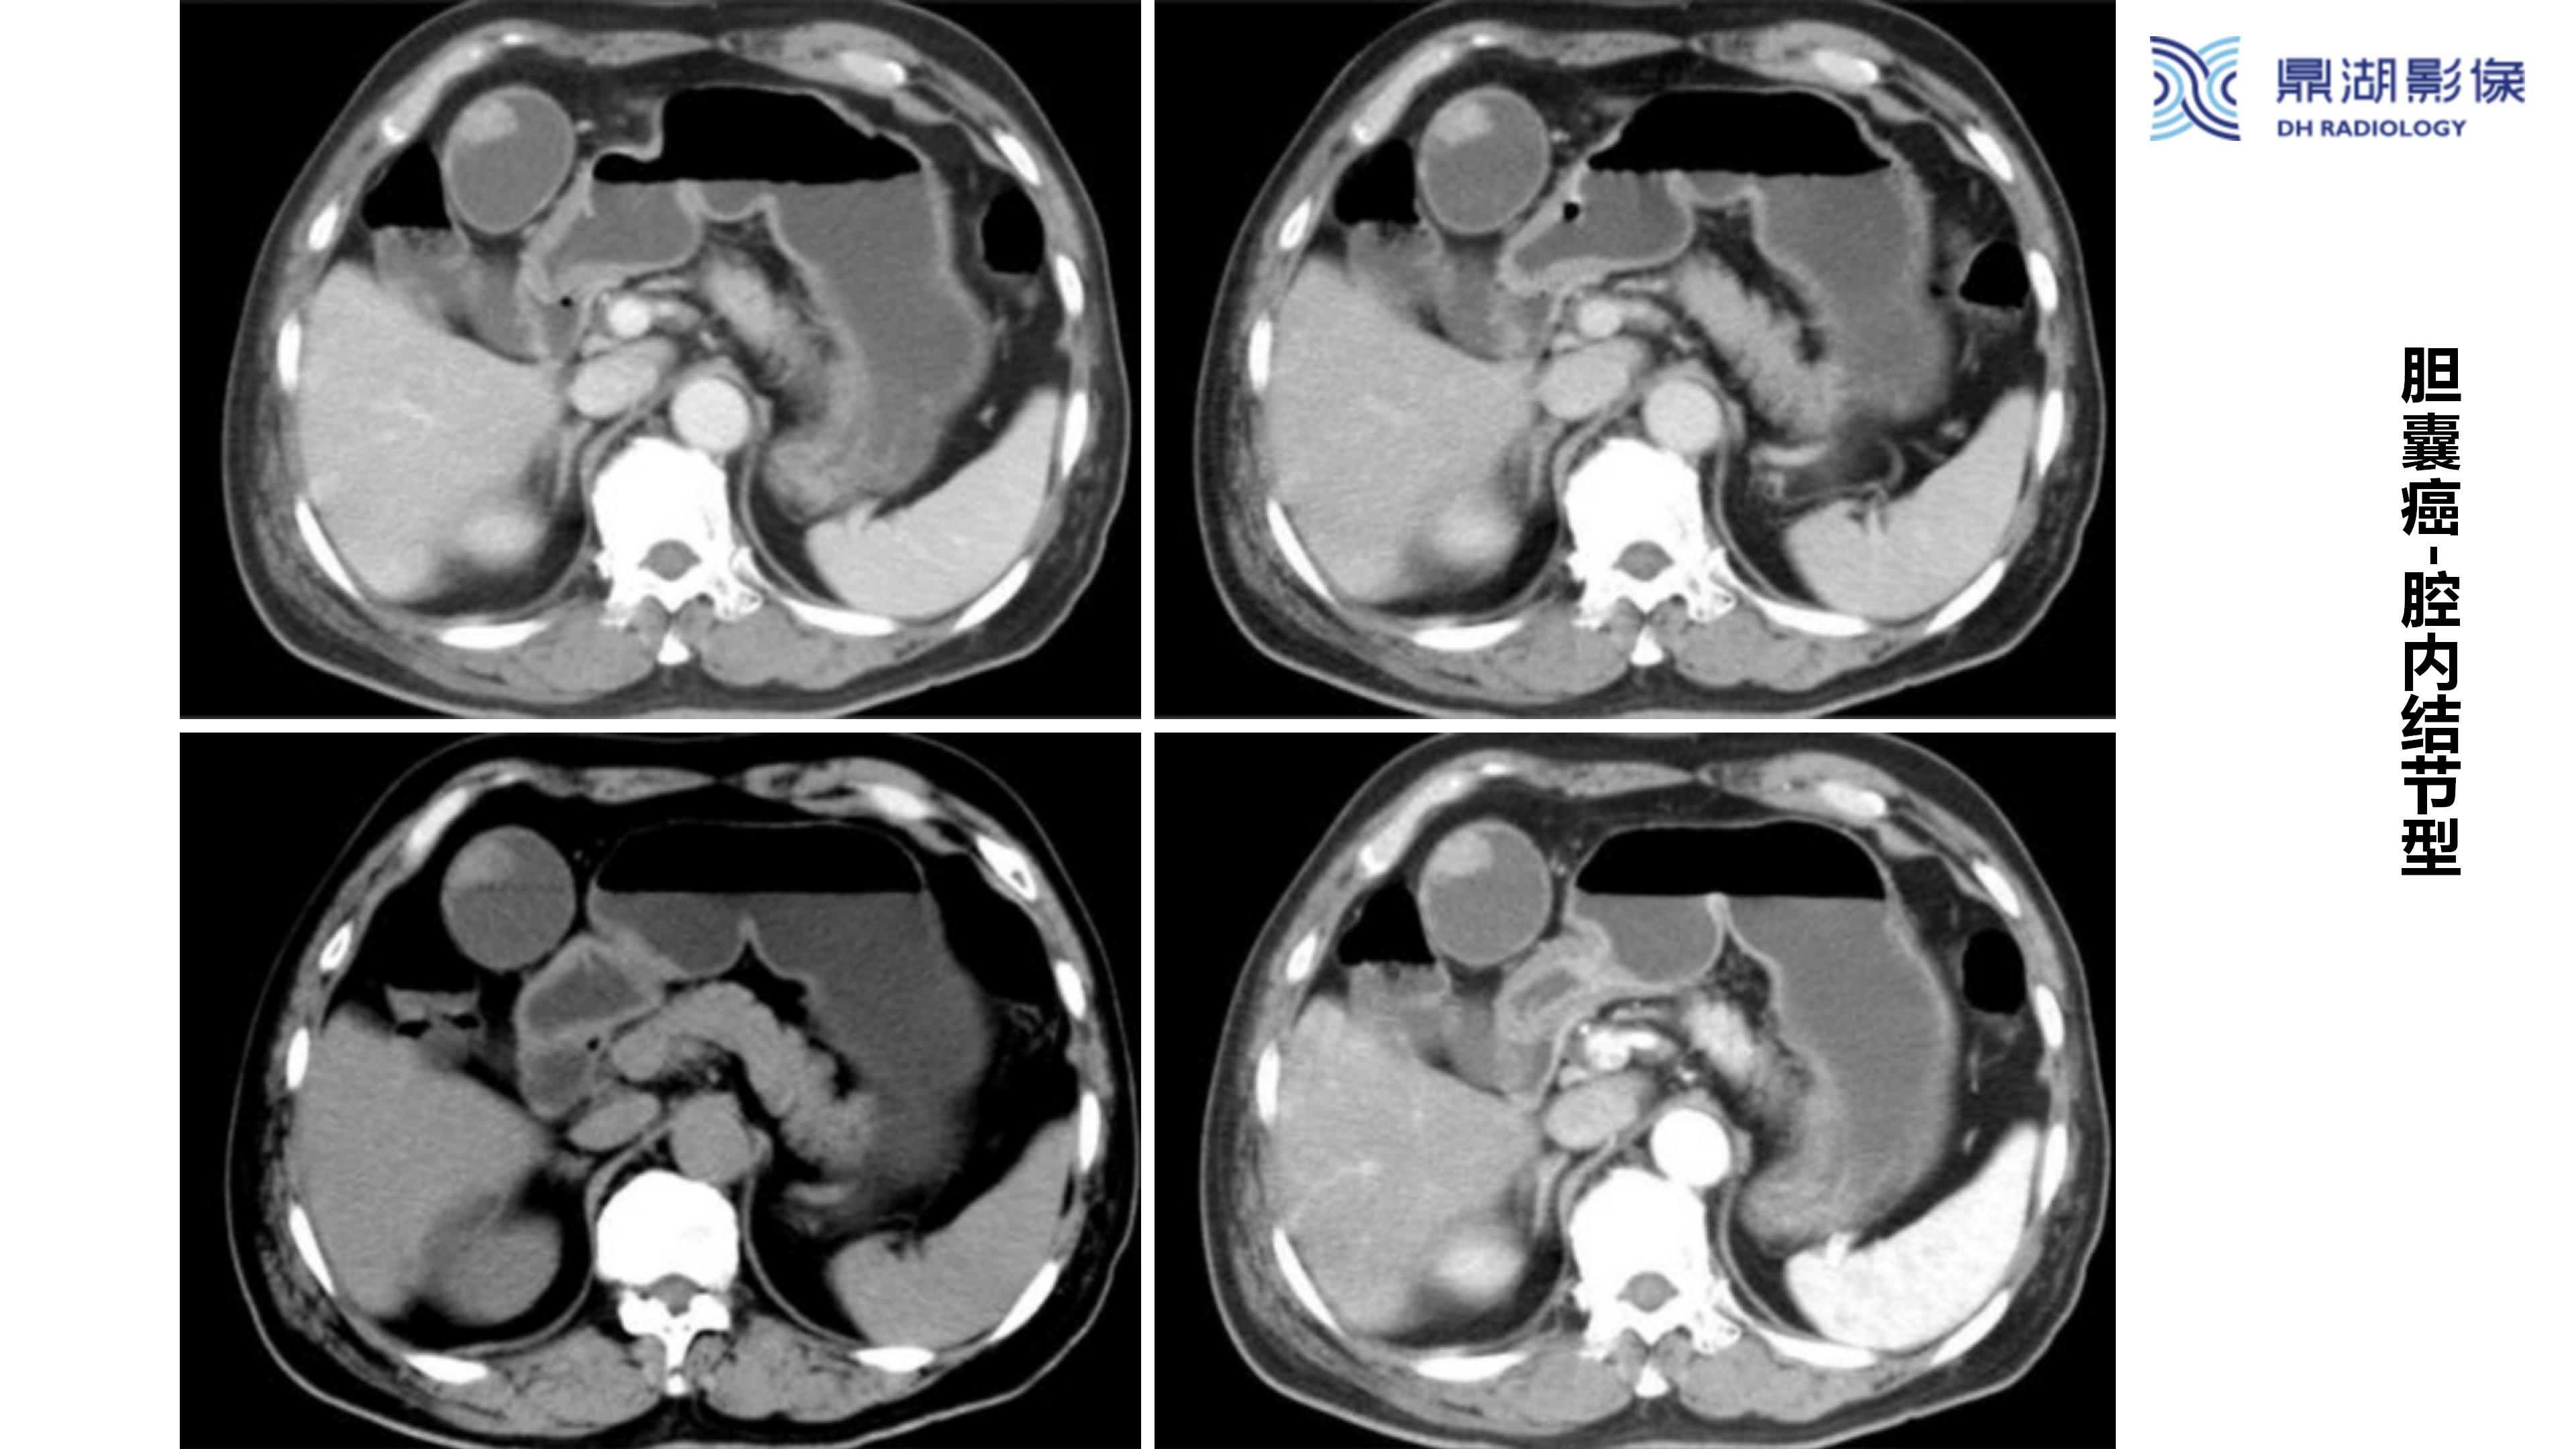

胆囊癌-鼎湖社群读片病例